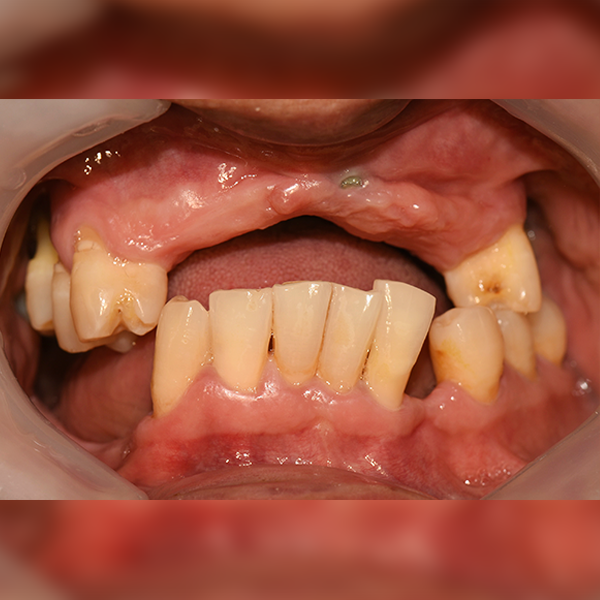

上顎/臼齒部位 / 3顆以下 / 補骨|舒眠

案例 188 50多歲 陳*英 2020-02-06 / 2020-12-11